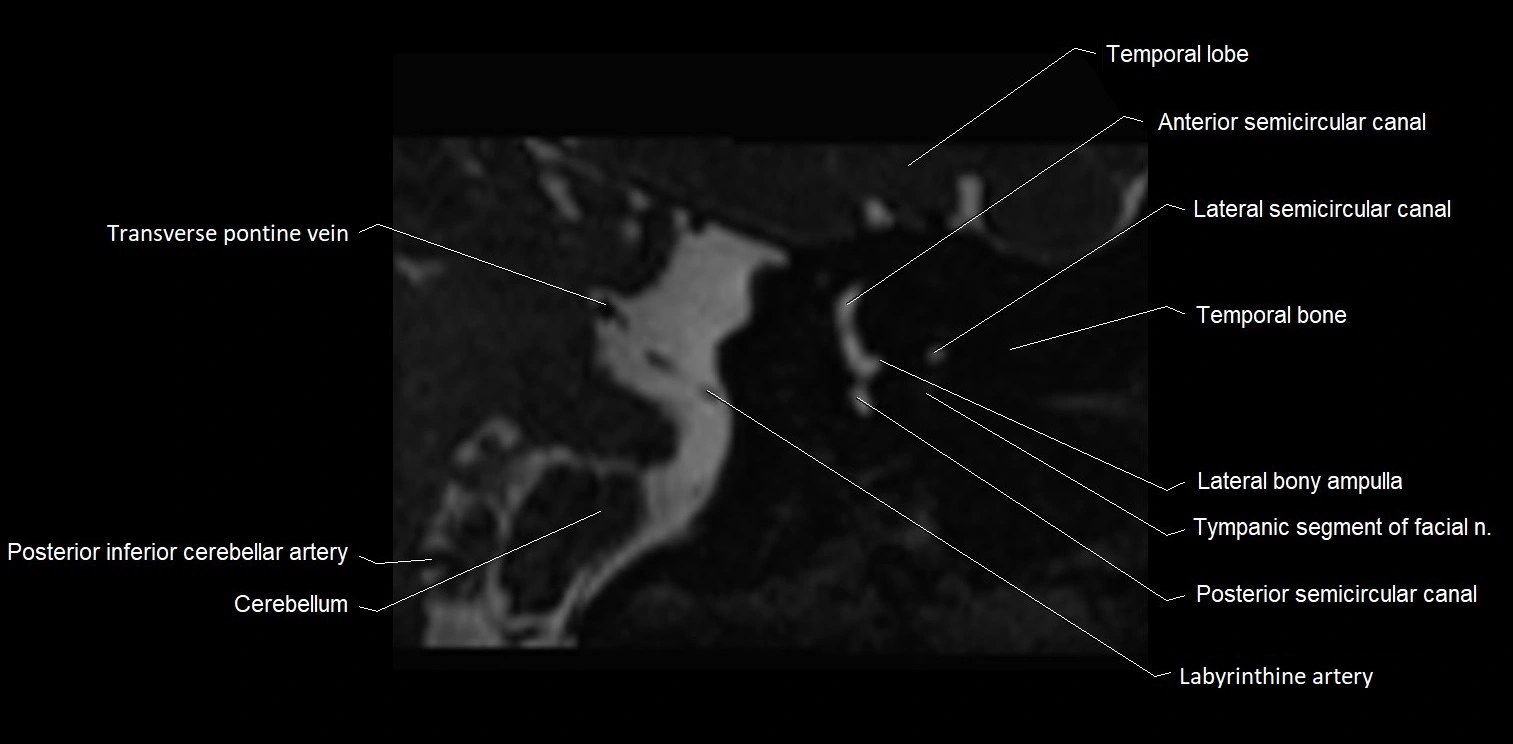

MRI images

image